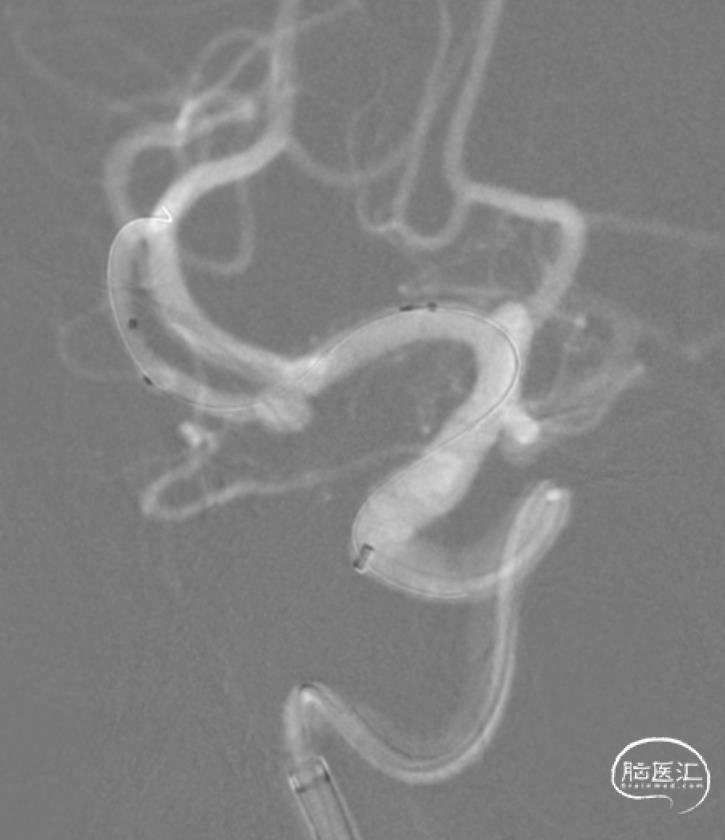

释放支架。

支架整个打开过程还是相当丝滑的。

SL-10穿网眼到达另一分支,备用。

弹簧圈栓塞。

造影分支血管良好。